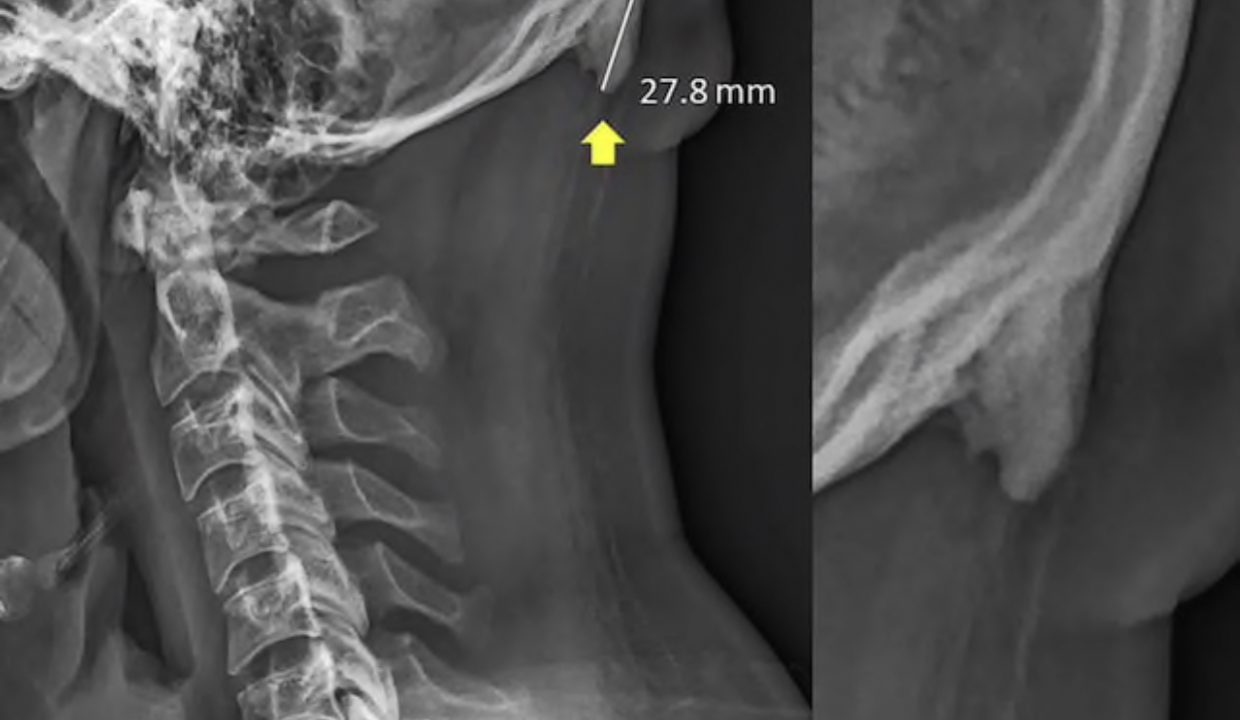

Это не шутка. Ученые из Австралии узнали, что при частом использовании смартфона у людей растут рога.

Да-да. Прямо на затылке развиваются рогообразные выступы из-за постоянно опущенной головы. Это приводит к смещению нагрузки от позвоночника к мышцам головы, отчего растут кости в сухожилиях и связках.

Зачастую такие отростки образуются у людей в возрасте от 18 до 30 лет.

Для формирования образований требуется много времени. Это означает, что люди с «рогами» использовали смартфоны с раннего детства.

Медики уверены, что перед нами серьезная деформация осанки, а не какая-то простая адаптация организма. Из-за неё могут выработаться хронические головные боли. [The Washington Post]